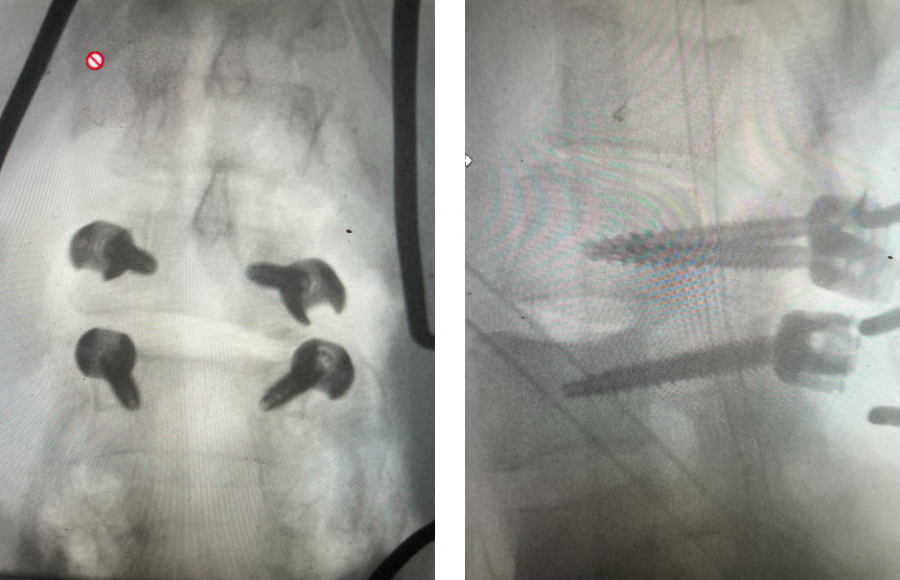

Revision surgery is more involved than primary surgery. In order to start decompressing this large complex, you must develop a plane; you have to find the edge of sometimes a remnant of a lamina or the lamina that can be buried in scar. You must carefully dissect the edge with a sharp upbiting curette and then either using a sharp Leksell to start removing this lamina or use a fine Kerrison to widen the plane and exposure and begin to expose the normal ligamentum above. In this case it was critical to expose and decompress the L3 nerve roots bilaterally. What is quite helpful is finding the inferior edge of the L2 facets. Then one must lift up the inferior L2 process up with a curette and simultaneously insert a Kerrison into joint space and remove the whole facet process. This is a great move because it allows access to the plane between the superior facet and the descending nerve root and a starting point to fully decompress the nerve root. Because of scarring there often is not a clear plane in order to accomplish the decompression. Care is taken to make sure there is a clear separation between edge of bone and dura during the process of inserting a Kerrison edge. The important part of this is feeling your opening and actually using your Kerrison as a dissecting tool once an edge has been established to perform a foraminotomy. We were able to remove the inferior L2 facet process with impunity as we knew we were performing an instrumented fusion to L2. The patient’s had a prior L3-5 instrumented fusion which upon exploration was solidly fused. It was decided to remove her prior hardware as it served its purpose and add a short segment from L2-3 (Fig 5). Patient did well after her surgery with relief of her right leg pain.

Fig 5: intraoperative fluoroscopic images demonstrating L2-3 screw placement.